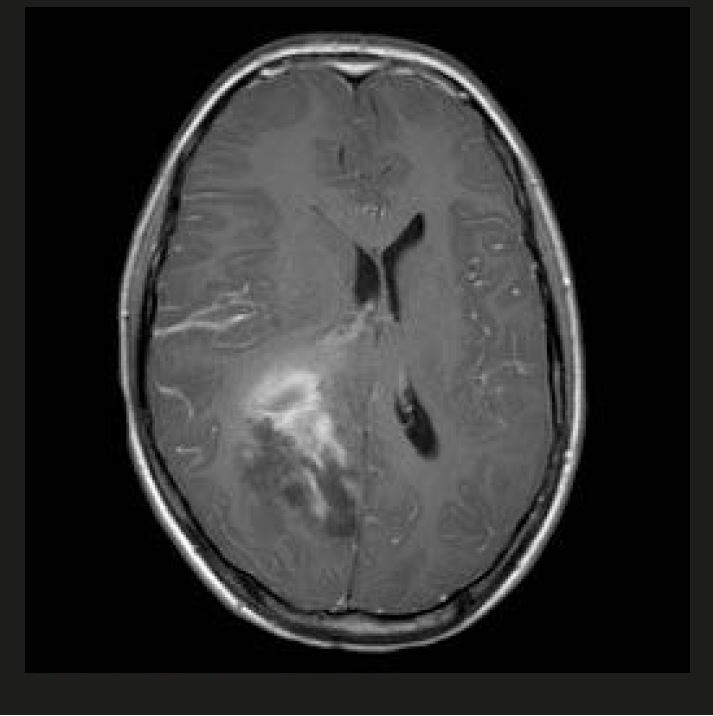

При неврологічному огляді виявлено двобічний набряк зорового нерву, двобічний парез 6-го черепного нерва, геміанопсію. Його одразу направили на МРТ. Було виявлено велике пухлинне утворення, частково геморагічне, у правій тім’яній ділянці з значним мас-ефектом (рис. 1 і 2).

Рисунок 2 T1WI + GD, перше сканування